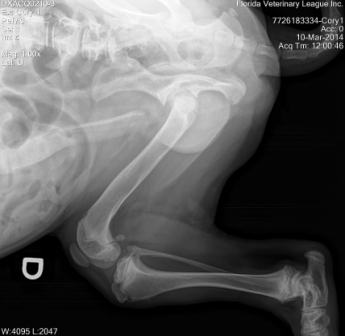

March 20, 2014

Cory is an unfortunate 7 month old puppy who was abandoned by his owner and unable to be adopted at an animal control facility due to a severe and debilitating defect on his hips and both rear knees/legs; Cory had two separate surgeries on each leg and He is able to walk now.

We are looking forward to providing this beautiful corgi baby with the opportunity to find a fantastic forever home.

Cory will never run or go for long walks like other dogs...He was also born with partial sight (vision) deficiency.Cory will always be a special need boy! Please stay tuned for future updates and thank you for supporting our rescue efforts!